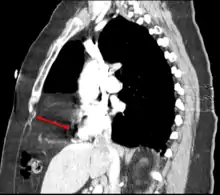

Morgagni hernia

CT of the chest demonstrates a Morgagni hernia (red arrow)

This rare anterior defect of the diaphragm is variably referred to as a Morgagni, retrosternal, or parasternal hernia. Accounting for approximately 2% of all CDH cases, it is characterized by herniation through the foramina of Morgagni which are located immediately adjacent and posterior to the xiphoid process of the sternum.[4]